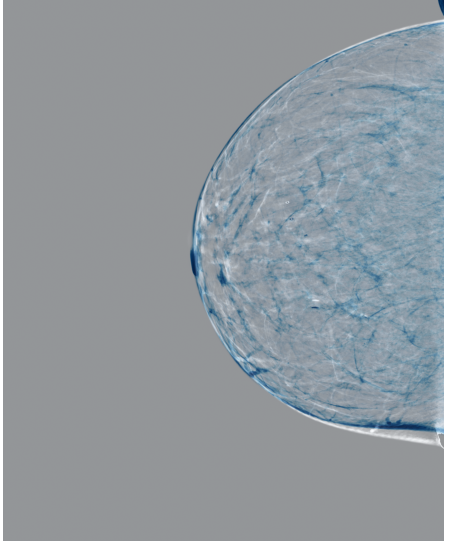

Refer to caption

(a) FeatAlign

(b) FeatAlignReg

(c) ImgFeatAlign/ImgAlign

(d) FeatAlign

(e) FeatAlignReg